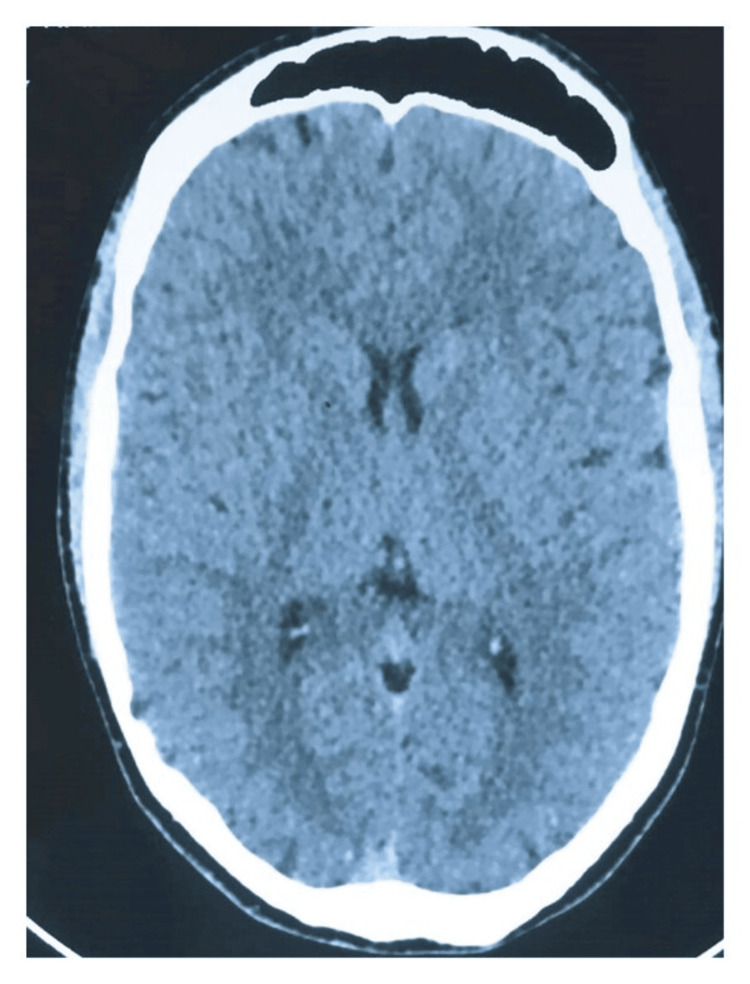

The patient had a history of recurrent nausea and vomiting occurring approximately once every three to four weeks, with episodes lasting two to three days, associated with epigastric abdominal pain, loss of appetite, and food intolerance for five years. Initially, these episodes were mild and sporadic but gradually became more frequent and severe over time. During this period, he had multiple consultations in primary healthcare and emergency departments and was even evaluated by general surgery. However, blood tests and imaging studies always showed no significant alterations (Figure 1). A CT scan performed during one of these visits was normal, effectively ruling out structural causes of the symptoms and increasing suspicion of a functional or substance-related disorder. Symptomatic treatment was provided. He was repeatedly diagnosed with anxiety disorder.